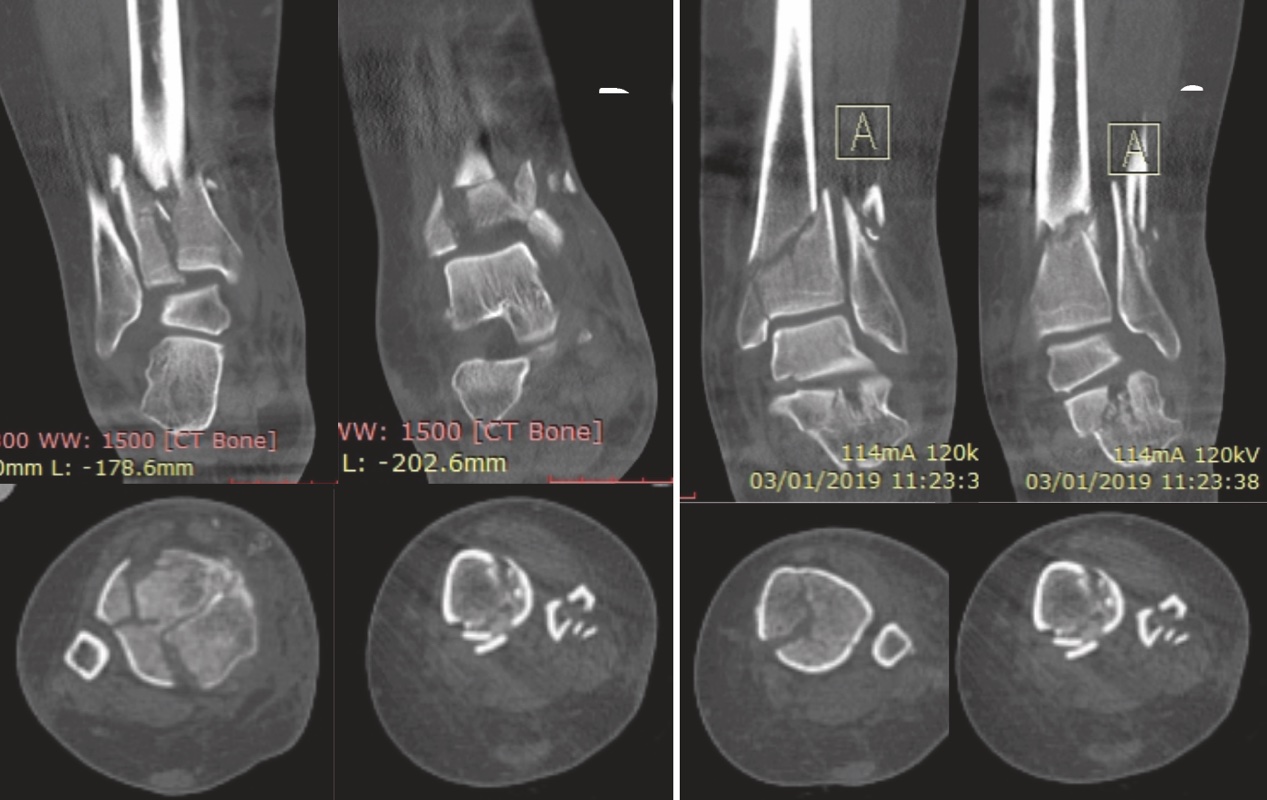

Il trattamento delle fratture di pilone tibiale deve essere accuratamente pianificato, le vie di accesso sono molteplici, il posizionamento del paziente può variare e la scelta dei mezzi di sintesi è particolarmente vasta. Per poter garantire il miglior trattamento al paziente è imprescindibile un accurato studio radiografico della frattura. La diagnosi può essere definita grazie alle classiche radiografie eseguite nelle tre proiezioni (AP, LL e AP obliqua) (Fig. 1).

). Questo esame di primo livello consente la classificazione della frattura secondo il sistema proposto da Ruedi e Allgower in tre stadi a seconda del numero dei frammenti e della scomposizione. Il sistema alfanumerico proposto dall’AO invece, classifica le fratture di pilone tibiale come 43B e 43C, cioè le fratture di tibia (4) distale (3) parzialmente (B) o completamente (C) articolari. La diagnosi eseguita tramite radiografia ci permette di passare alla prima fase del trattamento, cioè il posizionamento di un fissatore esterno temporaneo in distrazione associato o meno alla sintesi definitiva del perone. Una volta eseguita questa prima fase il paziente può essere sottoposto all’imaging di secondo livello con TC secondo il protocollo “Span & Scan”. La distrazione della tibiotarsica attraverso il fissatore esterno ci permette infatti, grazie a un meccanismo di ligamentotassi, un parziale riallineamento dei frammenti di frattura e di conseguenza un esame più accurato. Nel 2013 Cole et al hanno pubblicato un lavoro in cui, studiando nel dettaglio le scansioni assiali delle TC di 38 fratture di pilone tibiale, hanno potuto dimostrare la presenza di pattern più o meno comuni a tutti i pazienti 4. Il 100% delle fratture infatti aveva una rima che coinvolgeva la superficie articolare tibio-peroneale e da questa si dipartivano due linee di frattura (creando un pattern a Y) verso le porzioni anteriori e posteriori del malleolo mediale (Fig. 2).

Sono quindi di frequente riscontro tre macro-frammenti che possono essere definiti principali: un frammento mediale, uno antero-laterale e uno postero-laterale. La comminuzione è stata dimostrata nel 95% dei casi con presenza frequente di almeno un frammento impattato.